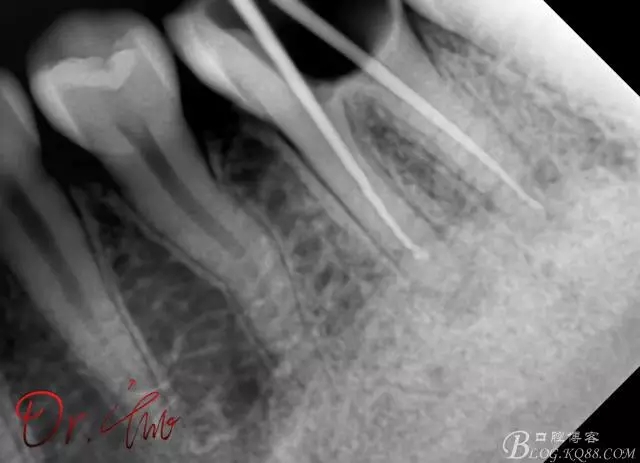

拍片確定長(zhǎng)度

640.webp (1).jpg